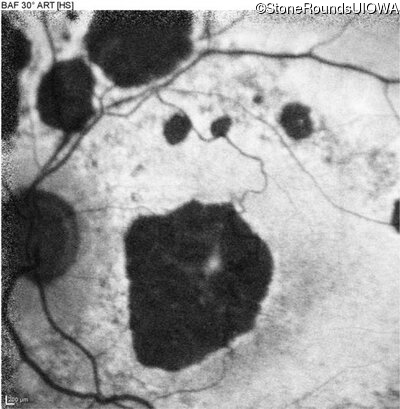

Blue Autofluorescence - Right - 20/125 -2

Exemplar